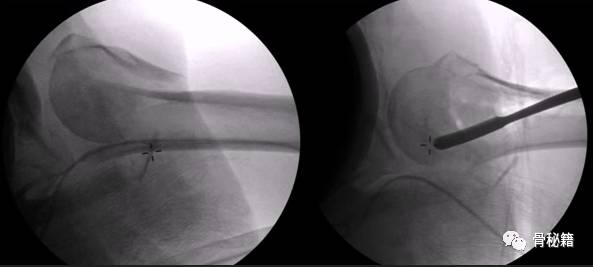

正位的翘拨复位

腋位的翘拨复位